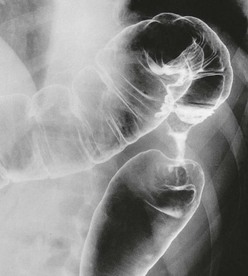

Fig. 27.3 Total mesorectal excision for low rectal carcinoma

Low carcinoma of rectum in a 70-year-old woman who presented with rectal bleeding and a change of bowel habit. A low anterior resection was performed with a covering loop ileostomy. The bowel was rejoined using the circular stapler. Two complete ‘doughnuts’ of tissue indicated successful firing of the stapler (see also Fig. 27.4)